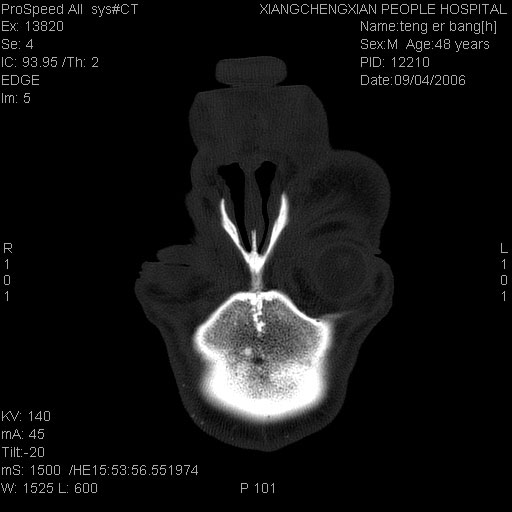

ct:平扫+冠扫:双侧鼻骨对比,冠扫s6#示右侧鼻骨尖部可见线状低密度影,边缘光滑,并见硬化.软组织未见肿胀.

诊断意见:鼻额缝(鼻骨与上颌骨额突缝),但个别同志认为是骨折.因此请同行们会诊.多谢了!

正常鼻颌缝。软组织无肿胀。鼻腔无积液积血。鼻骨光滑规整无中断。均不支持骨折。

正常鼻颌缝。软组织无肿胀。鼻腔无积液积血。鼻骨光滑规整双侧对称。均不支持骨折。